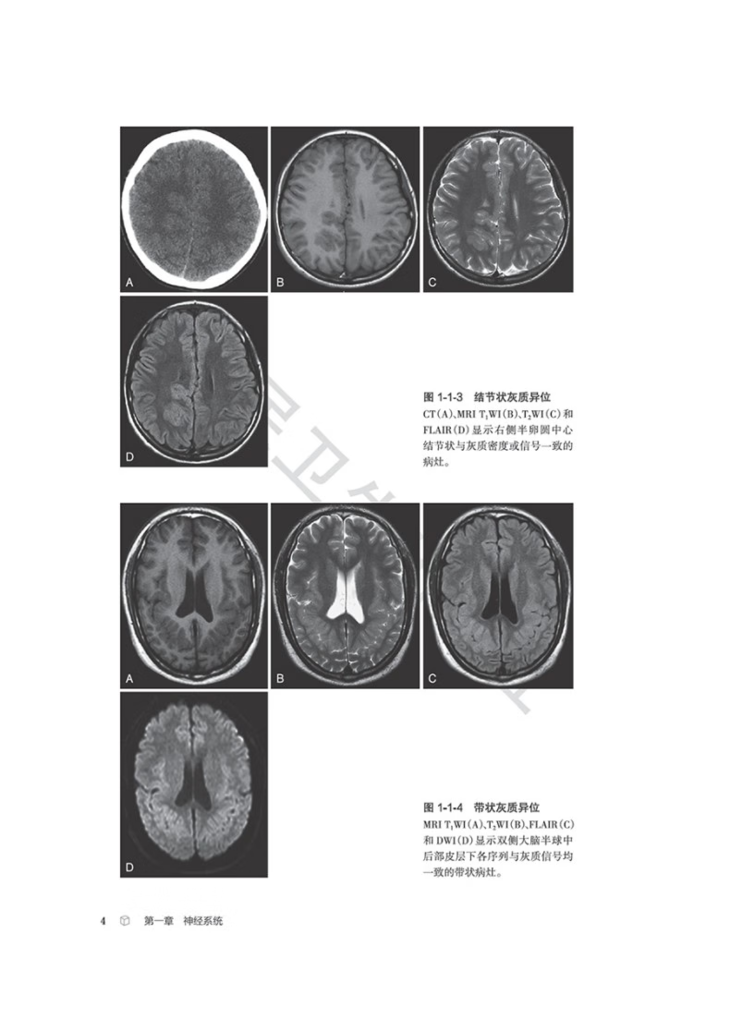

生殖系统、骨关节等影像科日常工作中的近300个常见征象,从每个征象的分析入手,凝练影像征象的特征,辅

以征象典型图进行说明,应用思维导图展现征象分析和诊断的思路,并融入鉴别诊断点和相应的疾病谱,抽丝剥

茧,去伪存真,示范从影像征象到诊断疾病的思维过程。